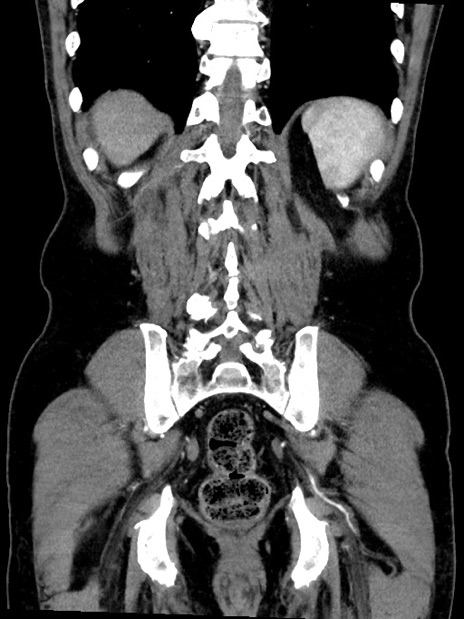

症例35(冠状断像)

【症例】70歳代 男性

【主訴】腹部膨満、嘔吐

【現病歴】昨日より腹部膨満感出現。本日増悪し、仙痛出現。嘔吐あり、受診。

【既往歴】糖尿病、胆摘後

【身体所見】BP 149/80mmHg、HR 74/min、BT 35.9℃、腹部:膨満、軟、圧痛なし。腸雑音減弱あり。上腹部正中切開瘢痕あり。

【データ】WBC 13500、CRP 1.72